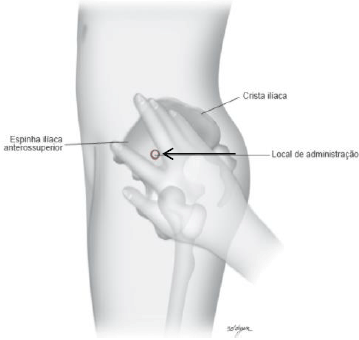

A figura abaixo mostra, com uma seta, um local de aplicação de injetável.

Fonte: CARMAGNANI, et al., 2019.

Indique abaixo, a alternativa que apresenta conteúdo correto sobre o local dessa aplicação.